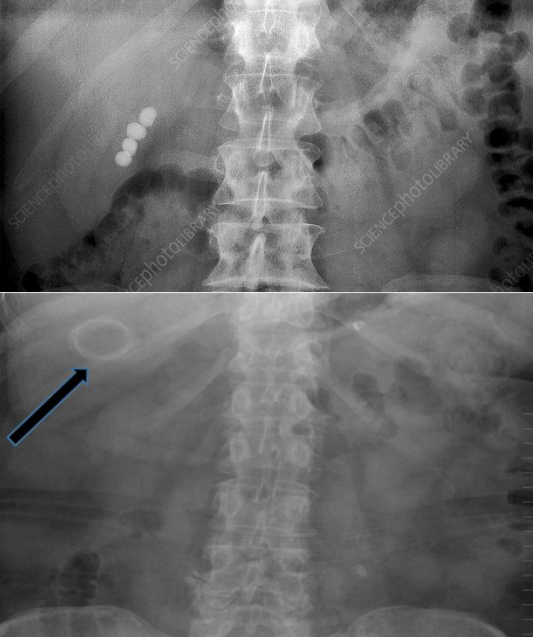

Q

¿Qué hallazgo radiográfico puede sugerir litos?

A

Radioopacidades redondeadas o en “capas de cebolla”